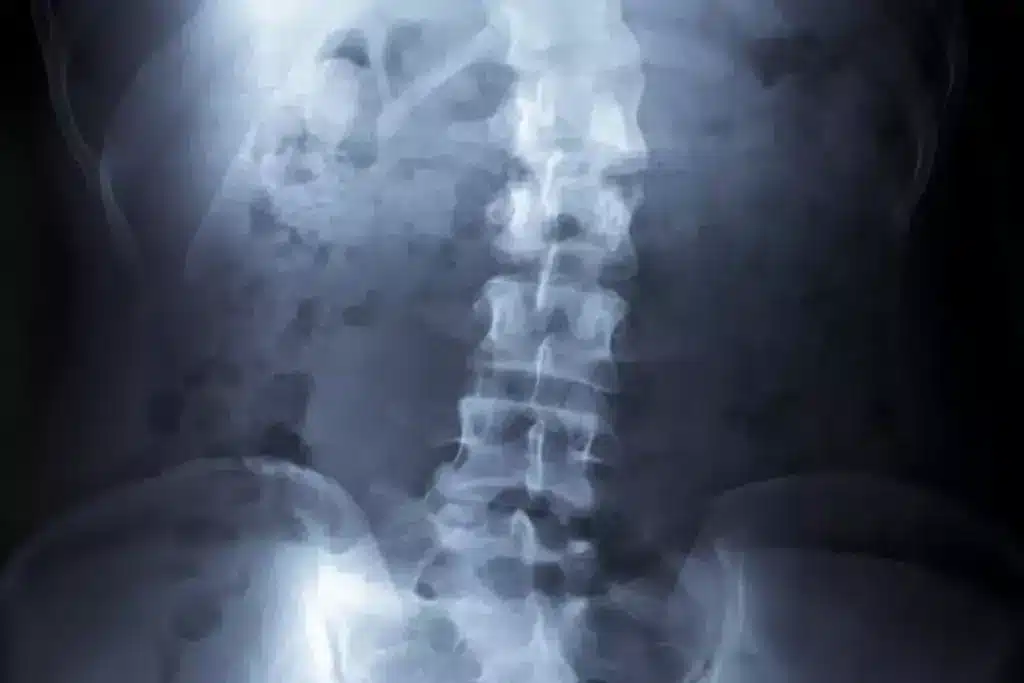

Measuring Curve Changes Over Time

Tracking scoliosis involves regular checks to see how the spine’s curve changes. X-rays are used to get a clear view of the spine’s alignment.

The Cobb angle is a key measure of scoliosis severity. It shows how much the spine is curved. Early detection and monitoring are key to managing scoliosis well and preventing serious deformity.